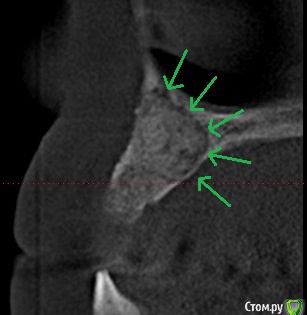

Дмитрий М Опубликовано 14 апреля, 2019 Поделиться Опубликовано 14 апреля, 2019 Пациент из другой клиники.До меня было удаление 12,11, 22 зубовВременная конструкция 13-11-23 Сделали цистэктомию 12, 22, резекцию 13, 23 после снятия швов пациент пропал на 9 месяцев, недавно пришел со снимком ) ОПГ область 12з область13з область 22з (зеленой стрелкой: непонятная "бяка" на снимке, в реале что-то вроде фиброзной капсулы было) область 23з Ссылка на комментарий

Дмитрий М Опубликовано 18 апреля, 2019 Автор Поделиться Опубликовано 18 апреля, 2019 кисты апексы 1 Ссылка на комментарий